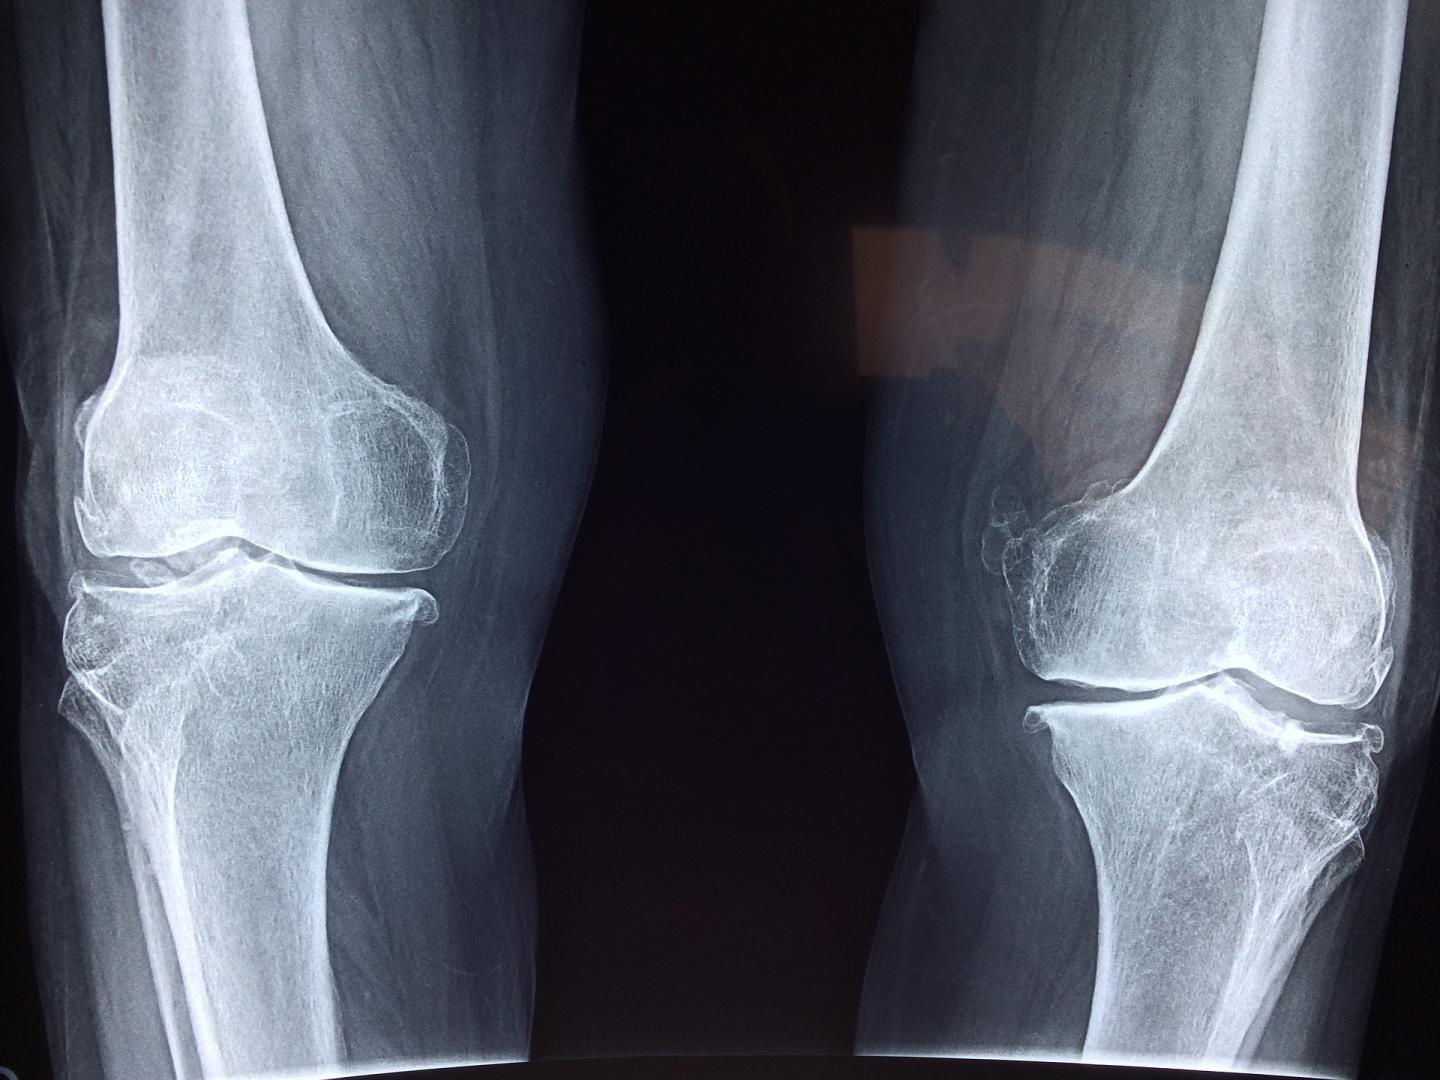

The skeleton is a highly dynamic structure that changes shape and composition throughout a person's life. Osteocytes are the most abundant cell type in bone but have proved difficult to study because they are embedded within the hard mineral structure of the skeleton.

Inside the bone, osteocytes form a network similar in scale and complexity to the neurons in the brain (with over 23 trillion connections between 42 billion osteocytes) that monitors bone health and responds to ageing and damage by signalling other cells to build more bone or break down old bone. Diseases such as osteoporosis and rare genetic skeletal disorders arise from an imbalance in these processes.